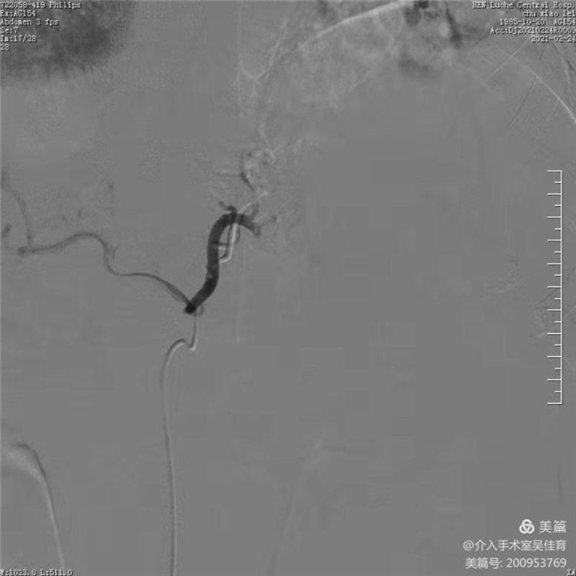

精确插管到胃左动脉

栓塞后胃左动脉闭塞,血流中断